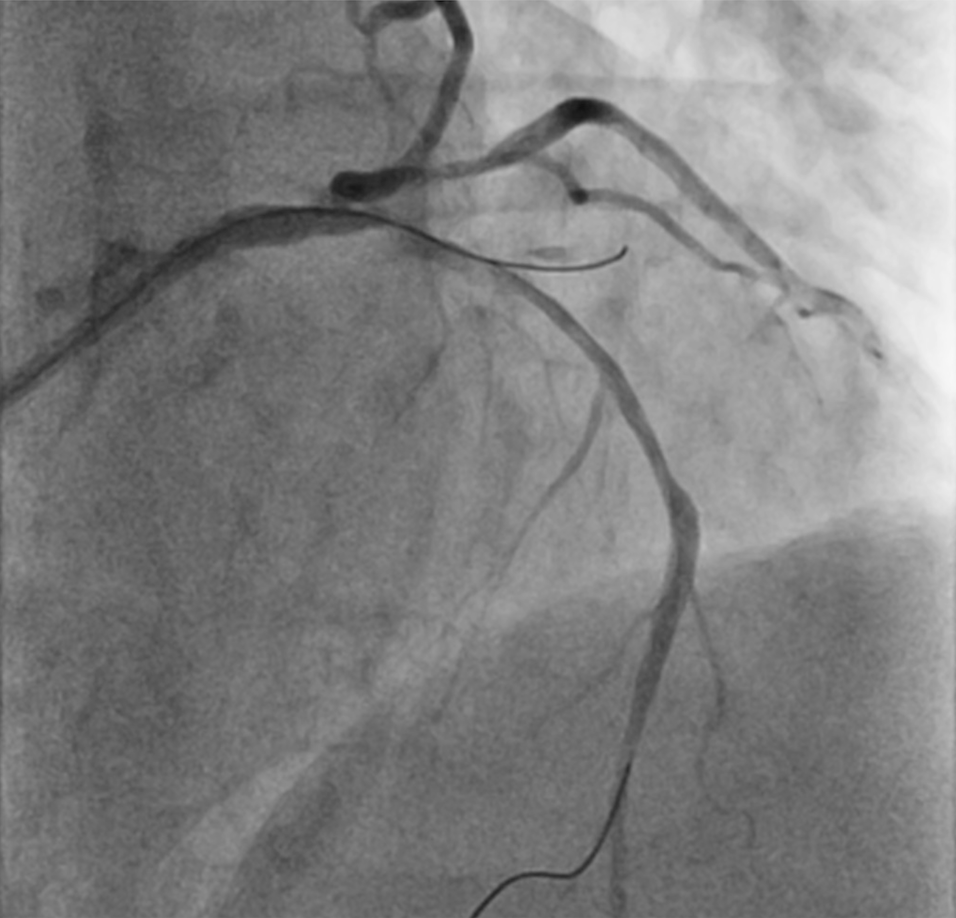

A 75-year-old man was admitted for non-ST-segment elevation myocardial infarction (NSTEMI). Coronary angiography showed focal severe disease at obtuse marginal artery (OM) and severe medina 1,1,1 bifurcation disease involving proximal to middle left anterior descending artery (LAD) and a sizable diagonal branch (Figure 1A, Video 1). With a 6-French extra backup (EBU) 3.5 guide catheter, the LAD was wired with a workhorse guidewire. The diagonal branch had a retroflex takeoff and initial wiring was subintimal (Figure 1B). Parallel wire technique (PWT) with Gaia Next 1 (Asahi Intecc) successfully rewired the true lumen and steered into the distal part of the diagonal branch (Figure 1C, D; Video 2). The LAD was provisionally stented with the diagonal branch protected by jailed balloon technique (JBT) of a 2.0 mm semi-compliant balloon, followed by stenting of the OM (Figure 1E). The final angiographic results were good (Figure 1F, Video 3).